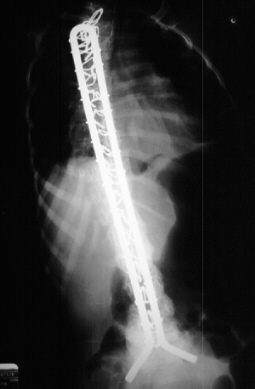

Age 6 scoliosis progressed to 78 degrees

and PSF with the unit rod

was performed.

Recommendation: Presently we recommend posterior spinal arthrodesis

with segmental fixation from T1 to the pelvis and currently use the Unit

Rod System.